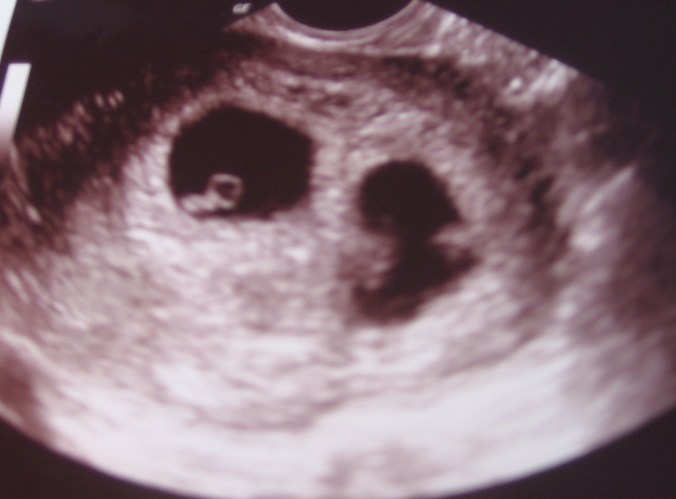

February 17, 2010 / 6 weeks

We are expecting TWINS – oh.my.goodness. What joy! What a surprise ~ what a miracle to hear two heartbeats yesterday! Psalm 37:4 “Delight yourself in the Lord, and he will give you the desires of your heart.” I can’t help but connect this to my secret hope and desire that I’d have twins. I’ve always wanted to have twins, and it really does feel like a dream come true! (I’m sure I’ll need to be reminded of that when I’m in such intense discomfort and we’re getting no sleep …!)

I am quite thankful that (a) we found out so early into pregnancy because it takes me forever to process big news and this was the biggest news of my life and (b) Seth was with me at the appointment and that he was sitting down. It was only one of a handful of moments I’ve seen him being entirely surprised. (The first was when I told him that I was in fact interested in dating him. This was a month after I’d instructed him not to ask me out on a third date because I wasn’t interested nor were we emotionally connected. But that will be for another series.)